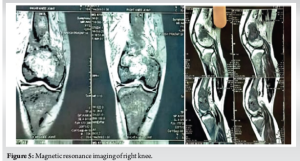

Radiological findings

Radiographs of the thigh revealed a right-sided pathological fracture of the distal femur along with generalized demineralization, bony cysts, osteolysis, and brown tumor (Fig. 1). X-rays of the forearm and hand showed lytic expansile lesions of the 2nd, 3rd, and 4th middle and distal phalanges (Fig. 2). X-ray of the skull revealed multiple lytic lesions with a “salt and pepper” appearance (Fig. 3). Ultrasonography (USG) of the right knee showed an ill-defined hypoechoic heterogeneous lesion on the medial aspect of the lower end of the femur with increased vascularity. USG of the neck revealed an oval iso to a hypoechoic component in the left lower neck, measuring 23.3 × 9.7 × 20.3 mm (Fig. 4). Magnetic resonance imaging of the right knee showed a large mass (7 × 2.9 × 5.8 cm) involving the distal end of the femur, including the diaphysis, metaphysis, and epiphysis, with a pathological fracture, soft tissue edema, and mild fluid collection in the distal thigh (Fig. 5). USG guided fine needle aspiration cytology of the lesion over the right distal femur was done which was suggestive of-giant cell-containing lesion. High-resolution computed tomography of the thorax revealed an expansile osteolytic lesion in the manubrium sterni, right head of the humerus, body of the right scapula, and multiple rib fractures. In addition, hypersensitivity pneumonitis, cardiomegaly, and mild hepato-splenomegaly were noted. USG of the abdomen showed mildly increased periportal echogenicity, a simple cyst (10 × 12 mm) at the midpole of the right kidney, increased bilateral renal echogenicity, and a few mesenteric lymph nodes (average size 10 × 5 mm) with maintained pancreatic hilar architecture. Although a sestamibi scan was highly recommended to confirm the diagnosis of PHPT, it was not performed due to the patient’s low economic status. The provisional diagnosis was a pathological fracture of the right distal femur with secondary osteoporosis at multiple levels caused by PHPT due to a suspected parathyroid adenoma.